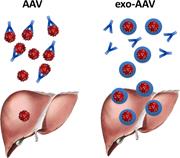

Enhanced liver gene transfer and evasion of preexisting humoral immunity with exosome-enveloped AAV vectors

Amine Meliani,Florence Boisgerault,Zachary Fitzpatrick,Solenne Marmier,Christian Leborgne,Fanny Collaud,Marcelo Simon Sola,Severine Charles,Giuseppe Ronzitti,Alban Vignaud,Laetitia van Wittenberghe,Beatrice Marolleau,Fabienne Jouen,Sisareuth Tan,Olivier Boyer,Olivier Christophe,Alain R. Brisson,Casey A. Maguire,Federico Mingozzi